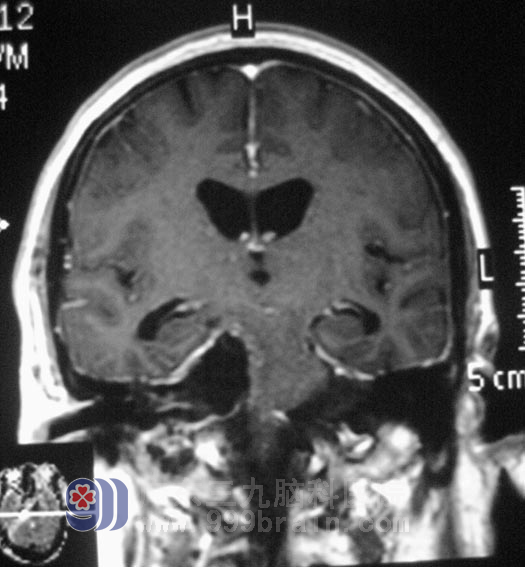

何阿姨的影像资料显示,肿瘤大小约3.0 cm *4.27 cm *3.18cm,初步诊断:1、右侧桥小脑角占位 (考虑脑膜瘤)2、脑积水 3、双侧基底节区腔隙性脑梗塞。完善相关检查后,3月31日,由鲁主任主刀在全麻下给何阿姨行右侧桥小脑角占位切除术+颅内压探头植入术,术中见肿瘤呈粉红色,质软,包膜完整,血供一般,显微镜下利用超声吸引器切除肿瘤,整个手术过程顺利。术后病理结果为:右桥小脑角区)纤维型脑膜瘤WHOI级,经过一段时间的住院治疗,何阿姨右耳的听力、视力、面部感觉都有所恢复,可以自主进食,已经康复出院。

手术后